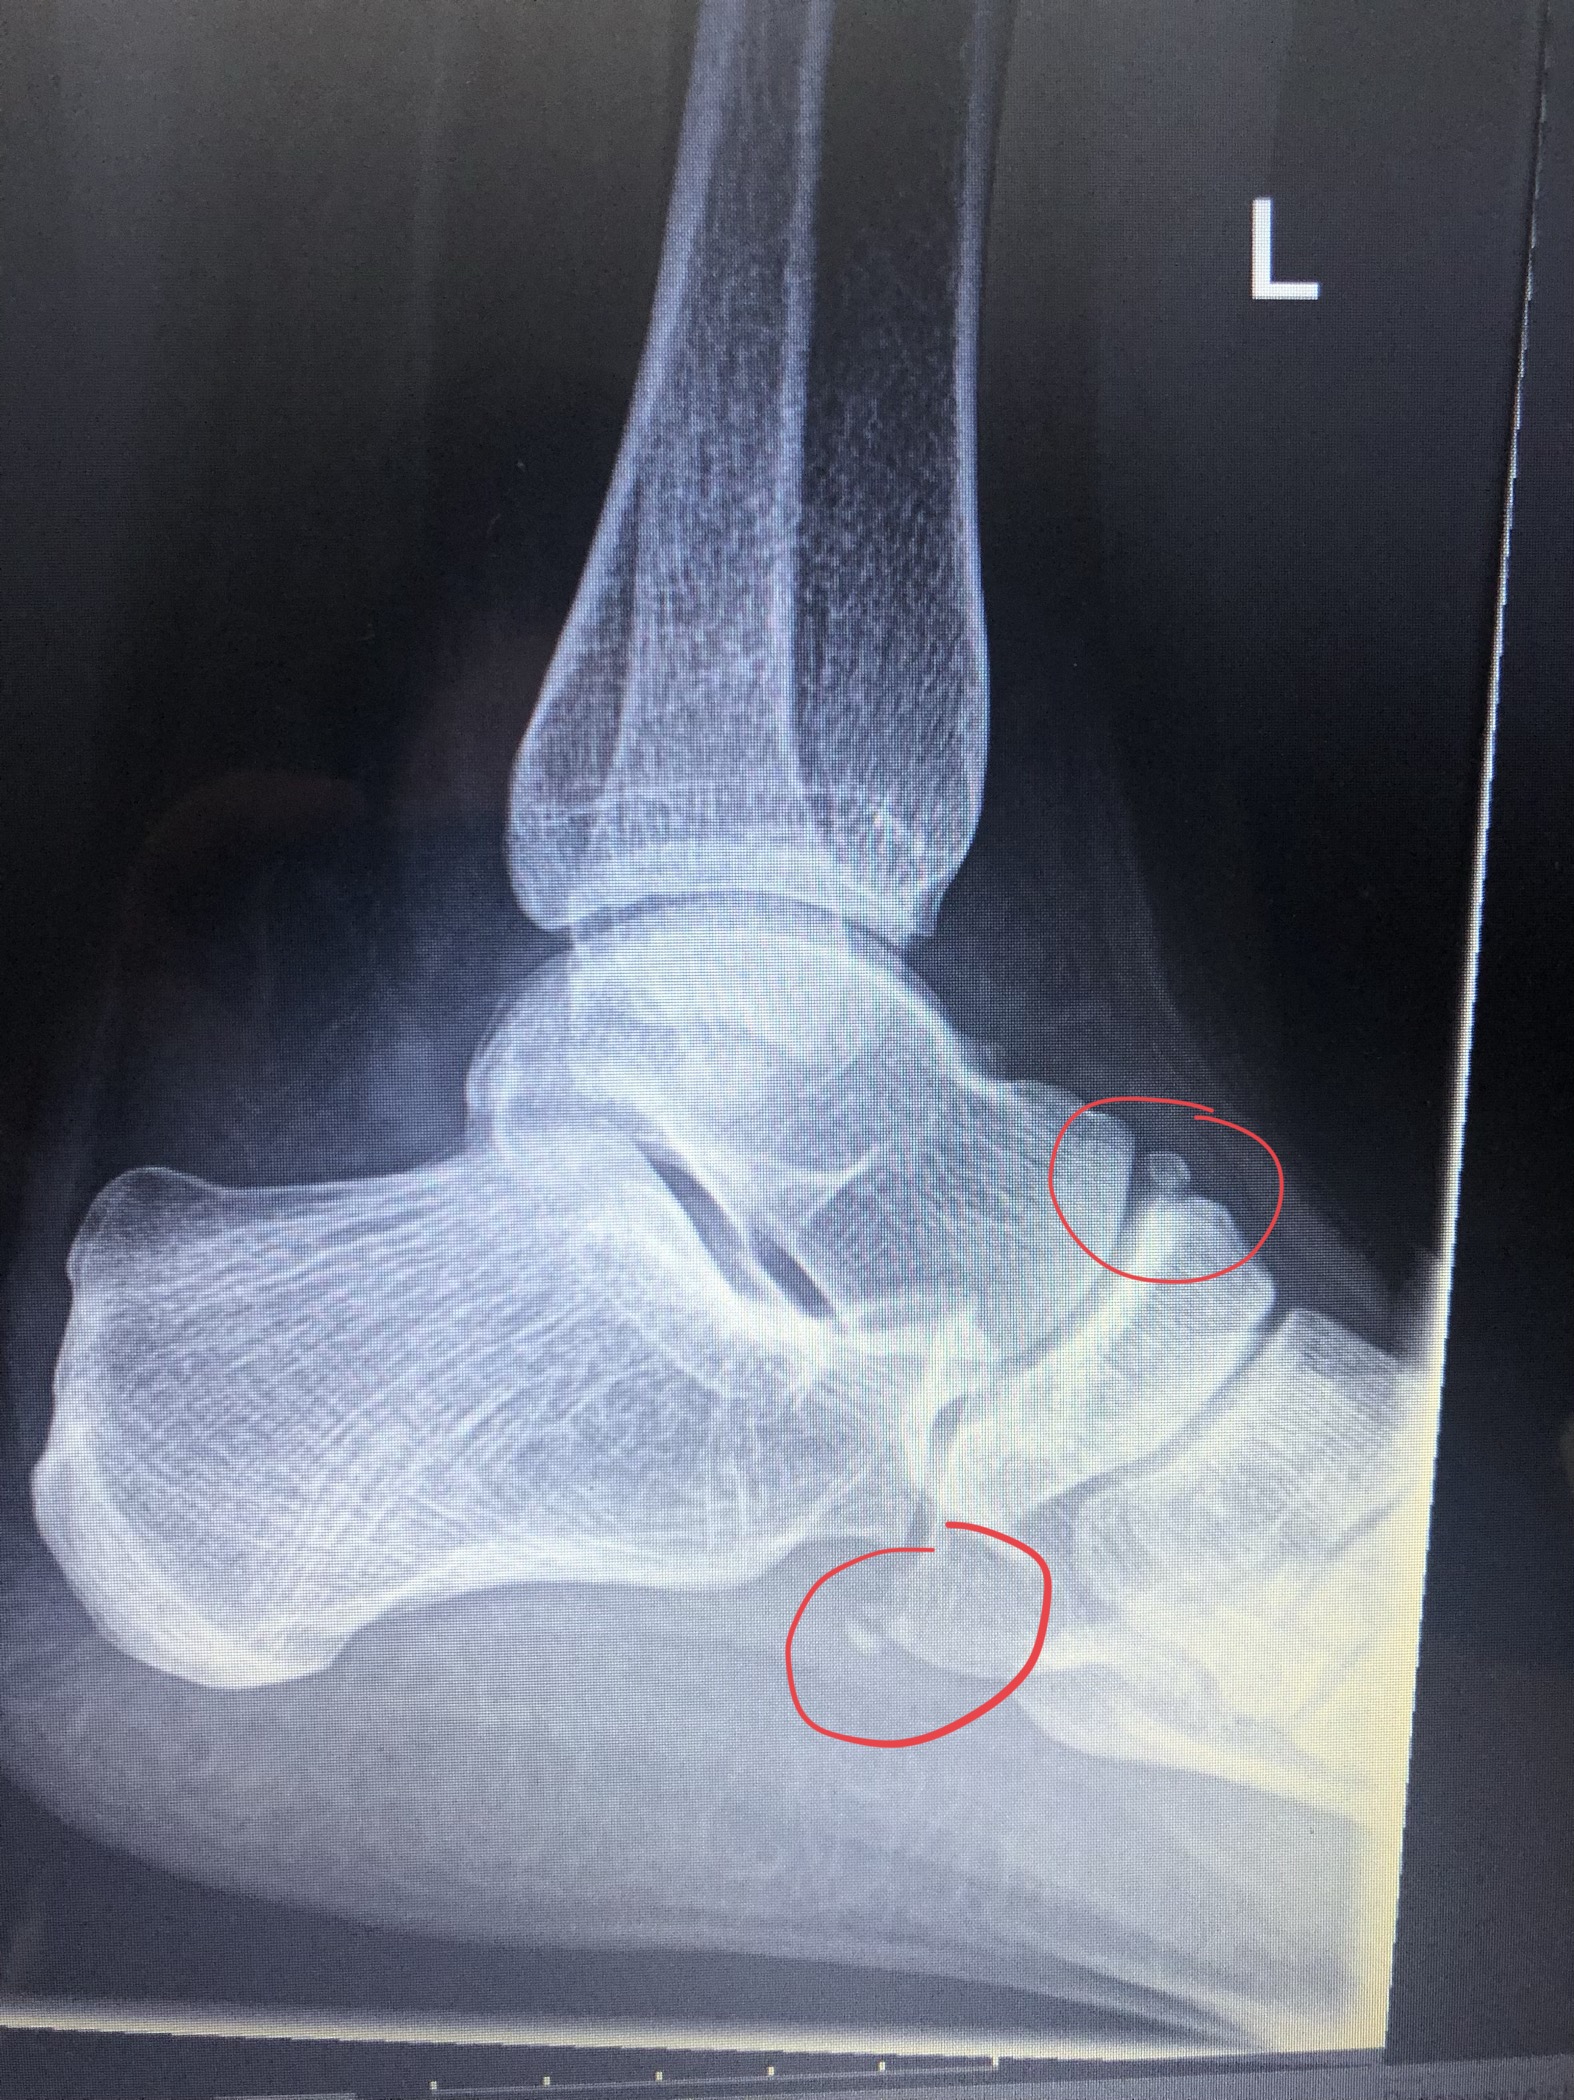

Fraktur Oder Bänderriss? (Schmerzen, Sprunggelenk)

Fraktur oder Bänderriss? (Schmerzen, Sprunggelenk) www.gesundheitsfrage.netSymptome Gaspoti